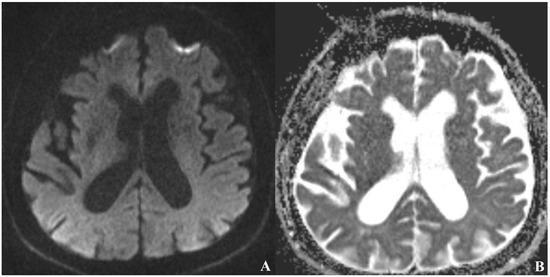

A 70-year-old male patient has presented with ongoing complaints of headache [VAS scale 6], pulsatile tinnitus [TFI level 3], and occasional dizziness. Neurological examination has revealed intact cranial nerves, bilaterally normal cerebellar function, normal deep tendon reflexes, a negative Romberg test, and preserved muscle strength. No abnormalities have been detected in other systemic examinations. Laboratory investigations showed no remarkable abnormalities. However, prior laboratory records indicated dyslipidemia for which the patient was under treatment, and he also had a known history of primary hypertension. Cranial MRI and MR angiography have demonstrated an absence of flow in the left internal carotid artery (Figure 1 and Figure 2).

Figure 1.

Absence of the left internal carotid artery on cranial MRI angiography [Time of Flight images (TOF), White arrow: no contrast filling in the carotid siphon].

Diffusion-weighted and T2-weighted MRI sequences have shown no pathological findings apart from age-related diffuse cerebral atrophy (Figure 4).

Figure 4.

No evidence of ischemia in the left hemisphere on diffusion-weighted MRI [(A) DWI, (B) ADC map sequence].